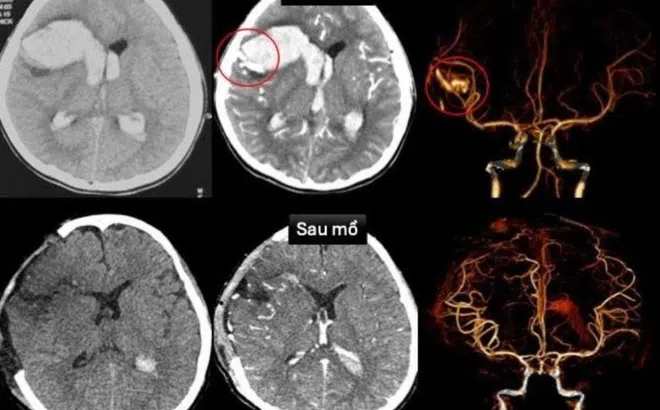

Bé gái TP.HCM vỡ mạch máu não, sốc tim nguy kịch khi đang ngủ

Bé gái 13 tuổi rơi vào hôn mê sâu, sốc tim nguy kịch. Kết quả kiểm tra khiến bác sĩ bất ngờ khi em cùng lúc mắc hai bệnh lý hiếm gặp ở não và tim.